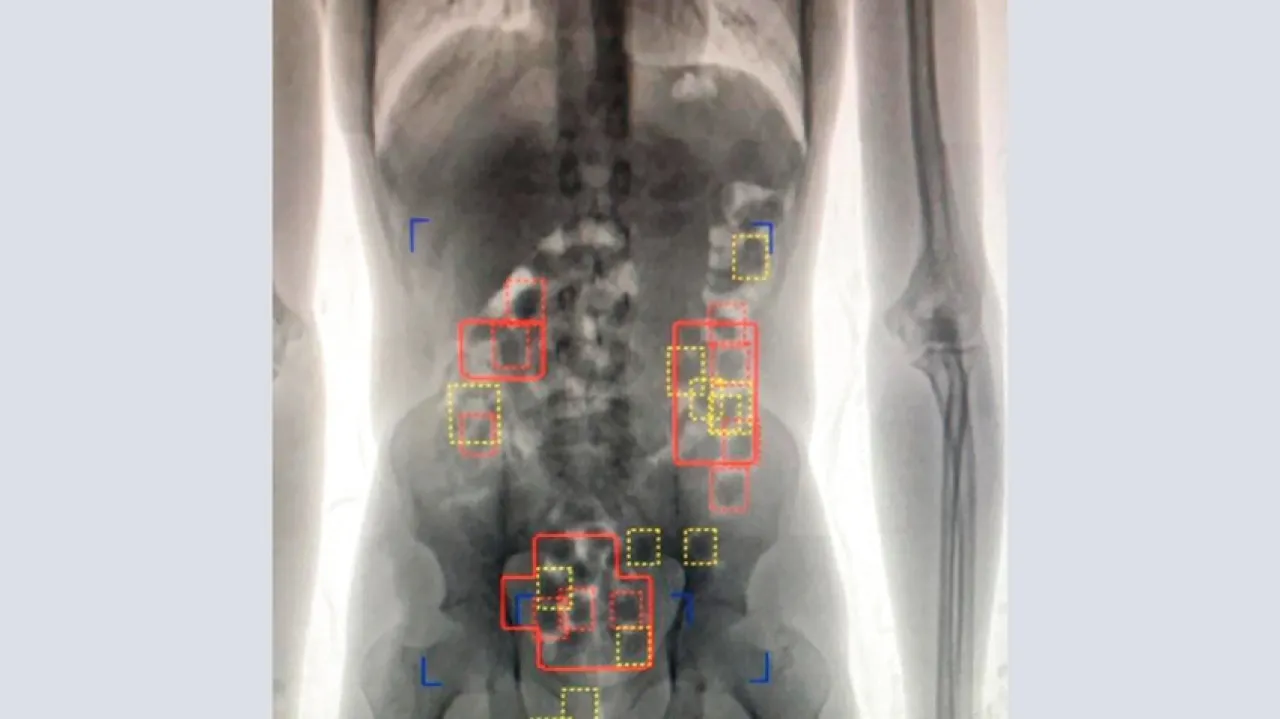

تم تفتيشه شخصيًّا وتفتيش أمتعته فلم يجد أي مواد مشتبه بها، ونظرًا إلى كون المتهم تبدو عليه علامات الارتياب، فقد تقرّر نقله إلى مستشفى السلمانية لعمل فحص بالأشعة والكشف عليه، وهناك تم التأكد أنه يحمل بداخل أحشائه أجساما غريبة، فقام الطبيب المسؤول بإعطائه أدوية مسهلة، فقام على اثرها بإنزال 90 كبسولة هي عبارة عما يقرب من نصف كليوجرام من المادة المخدرة.

وبفحص تلك الكبسولات تبين احتواؤها على مسحوق مادة الميتافيتامين المخدر موضوعة بشكل مضغوط، وقد اعترف المتهم أثناء التحقيق معه بأنه التقى شخصا في بلده، أعطاه الكبسولات ليبتلعها ويوصلها إلى أحد الأشخاص في مملكة البحرين؛ وذلك مقابل حصوله على 400 ألف روبية، وقد تبين أن شبكة لترويج المخدرات استخدمت المتهم في محاولة تهريبها ونقلها إلى البحرين.